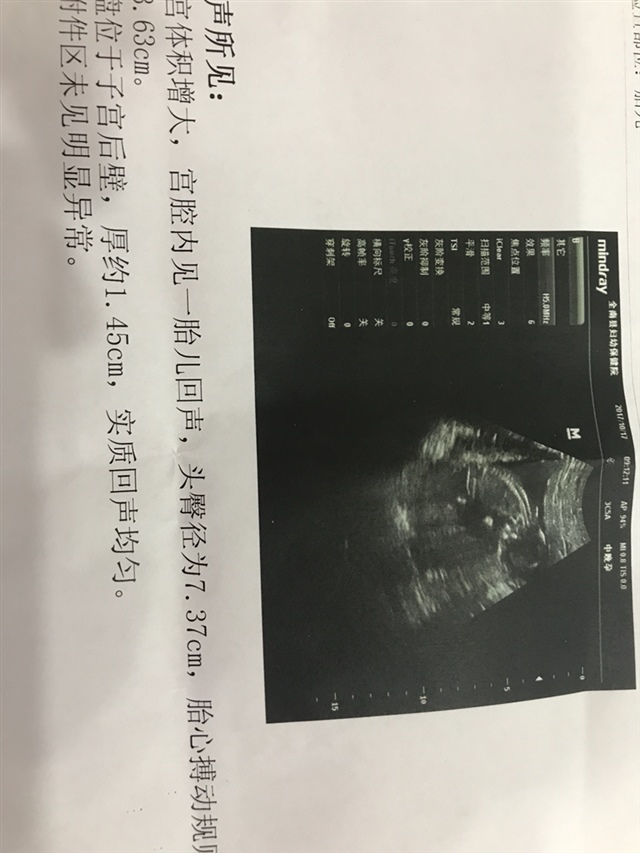

Fairy°Story°[帖主]:三个多月了